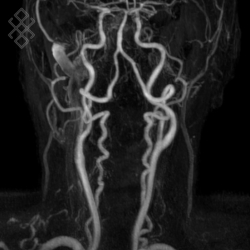

Angio-IRM des Troncs Supra Aortiques (TSA)

La durée moyenne de l'examen est de 35 min. Souvent, il est le complément de l'IRM cérébrale. Dans le cas d'une injection, le manipulateur en radiologie vous administrera le produit de contraste. Vous entendrez un bruit caractéristique à l'IRM faisant penser à un marteau piqueur. Pendant certaines séquences, pour limiter les mouvements de déglutition, il ne faudra pas avaler la salive.